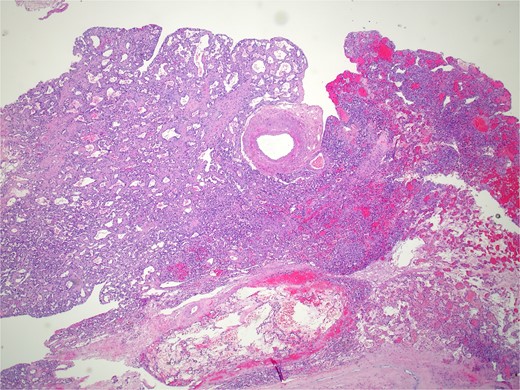

Pathology revealed a benign vascular neoplasm, whose morphological pattern favored AH (Figs 3 and 4).

Histopathology micro findings showing anastomosing proliferation of capillary-sized vessels with mild endothelial cell nuclear variability.